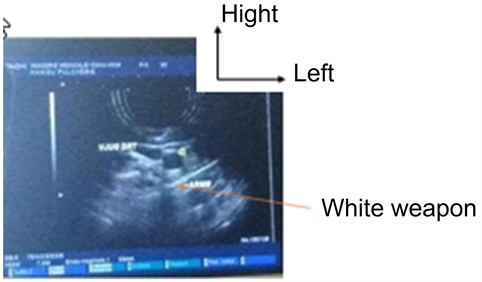

A cervical Doppler ultrasound showed the integrity of the jugulo-carotid vessels rights near the weapon (Figure 3).

Figure 3. Cervical Doppler ultrasound of the patient.

The patient’s cervical Doppler ultrasound showed the integrity of the right jugulo-carotid vessels near the weapon. It was requested at the first intention because it is the most accessible and the most available in our context. It is requested in an investigation report of a vascular lesion that manifests itself by a hematoma and can allow a postoperative control to evaluate the flow rate of the vascular flow [2] [5].